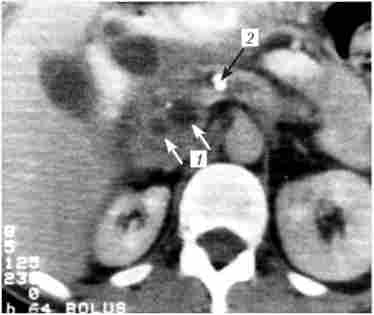

Комп'ютерна томографія (КТ) - рентгенологічний метод високої роздільної здатності, досить широко використовуваний при дослідженні ПЖ (рис. 20.7). В принципі, метод дозволяє отримати дані, аналогічні ехографічним, проте в ряді випадків дає можливість уточнити останні, наприклад при ожирінні хворого, наявності метеоризму, переважної локалізації патологічних змін в області хвоста залози.

Комп'ютерна томографія при хронічному кальціфіцірующем панкреатиті. На знімку видно кісти головки підшлункової залози (У), розширений вірсунгов проток і кальцинат в його просвіті (2)

Мал. 20.7. Комп'ютерна томографія при хронічному кальціфіцірующем панкреатиті. На знімку видно кісти головки підшлункової залози (У), розширений вірсунгов проток і кальцинат в його просвіті (2)

Разом з тим зустрічаються випадки, коли осередкові зміни, виявлені при УЗД, не виявляються при КТ (ізоденсни) або навпаки (ізоехогенние). Таким чином, обидва дослідження доповнюють один одного. З огляду на високу вартість КТ, її застосування слід вважати за необхідне у випадках, коли на підставі УЗД не вдається створити досить чітке уявлення про патологічні зміни в підшлунковій залозі (наприклад, коли в підшлунковій залозі виявляється частково ізоехогенние вогнище).